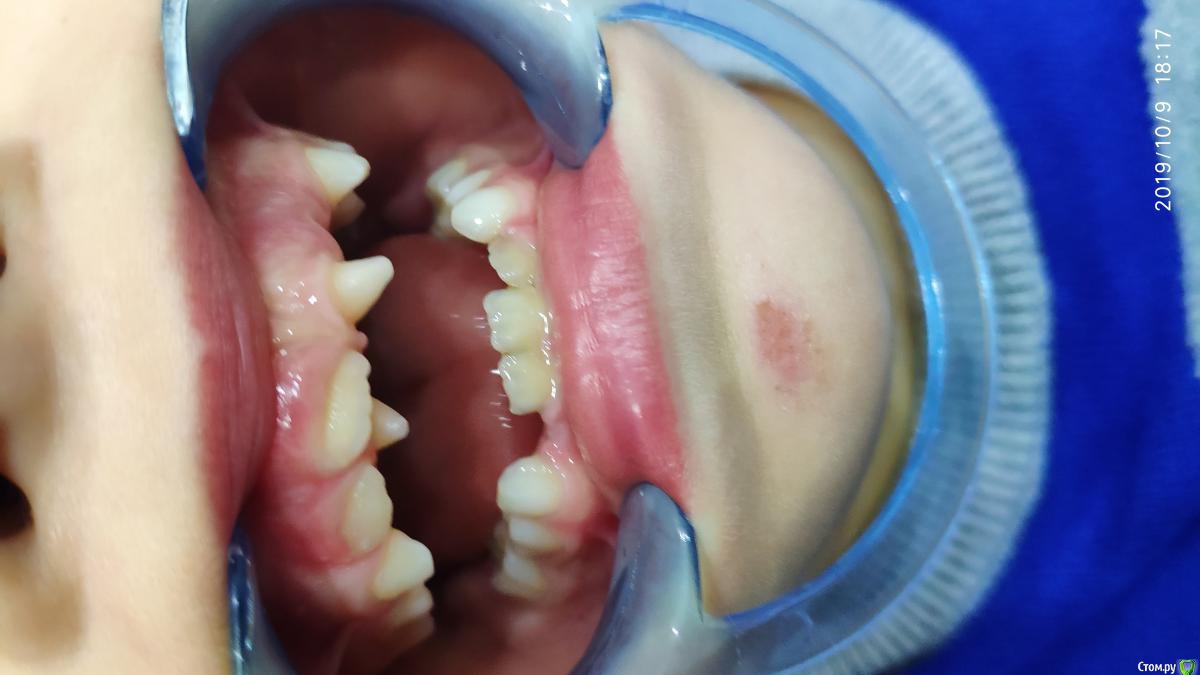

dr.i Опубликовано 11 октября, 2019 Поделиться Опубликовано 11 октября, 2019 (изменено) Нужна помощь в определении как быть в этой ситуации мне кажется здесь сверхкомплектные зубы,и скорее на удаление пойдут эти два зуба.что можете сказать по этому поводу. Изменено 11 октября, 2019 пользователем dr.i Ссылка на комментарий